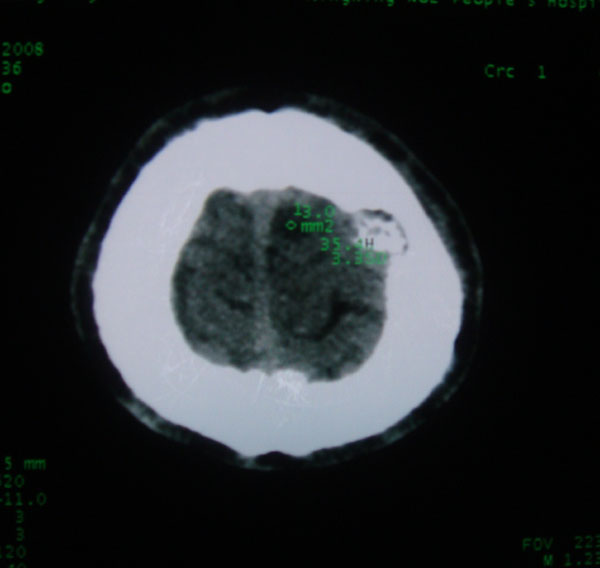

以下是引用拾荒者在2008-6-7 13:05:00的发言:[br]左侧顶骨局限性骨质缺损,边缘锐利,无硬化边,周围软组织轻度肿胀,无明显软组织肿块及骨膜反应,考虑嗜酸性肉芽肿可能。